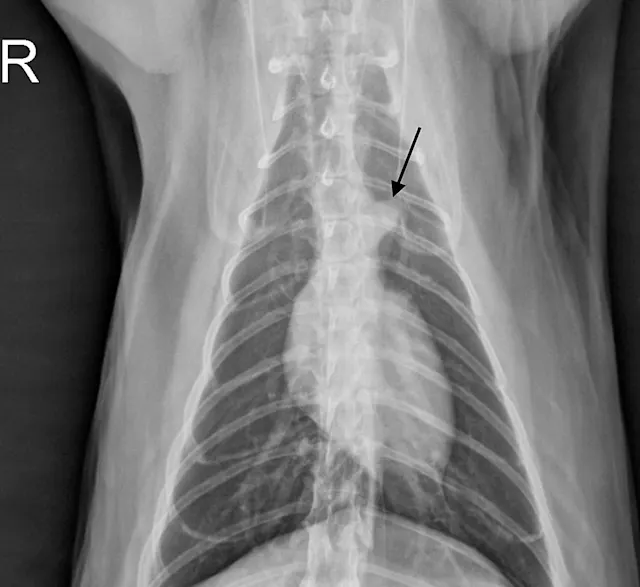

Thoracic radiographs are generally difficult to assess in cats due to age-associated variability. The cardiac silhouette develops increased sternal contact as cats age (Figure 1), with the aorta creating a notch or right-angled appearance that can falsely suggest left atrial enlargement on ventrodorsal projection. The aortic arch may have a rounded appearance on the ventrodorsal projection that can be mistaken for a pulmonary nodule in the left cranial lung lobe (Figure 2).1

FIGURE 1A

Lateral radiographs of a 2-year-old cat (A) and a 9-year-old cat with increased sternal contact of the cardiac silhouette (B).